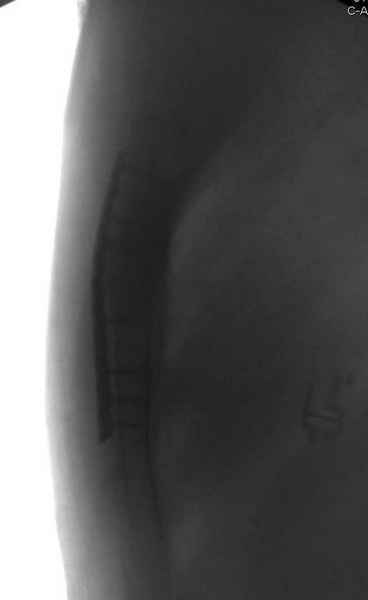

А простые посттравматические ложные суставы грудины приходилось оперировать с ограничителем сверла и с фиксацией 2.4 мм пластинами с угловой стабильностью.